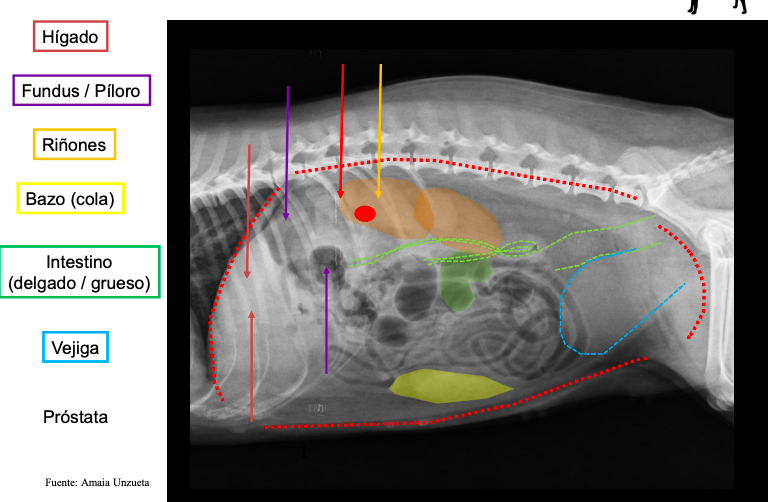

esofago no se ve en radiografias. De craneal a caudal:

- Higado vesicula biliar a la derecha

- Estomago con pancreas

- Bazo (fundus a la izquierda, cola a la derecha en perros, gatos se mantiene medio-izquierdo)

- intestinos (asas intestinales) Colon ascendente derecho, descendente izquierdo

Radiografia laterolateral

Dependiendo de la posición los gases van a un lado o a otro: Decúbito lateral derecho Radiografía Lateral

- Gas en fundus

- Se ve mejor cola del bazo

- Mayor separación de siluetas renales

Decúbito lateral izquierdo

- Gas en píloro

- Mejor visualización delduodeno

Radiografia ventrodorsal

Estómago e Hígado Radiografia Laterolateral y Ventrodorsal

- Eje estómago: perpendicular a la CV, paralelo a las costillas o en una posición intermedia

- Hígado: tamaño, contorno, localización y densidad